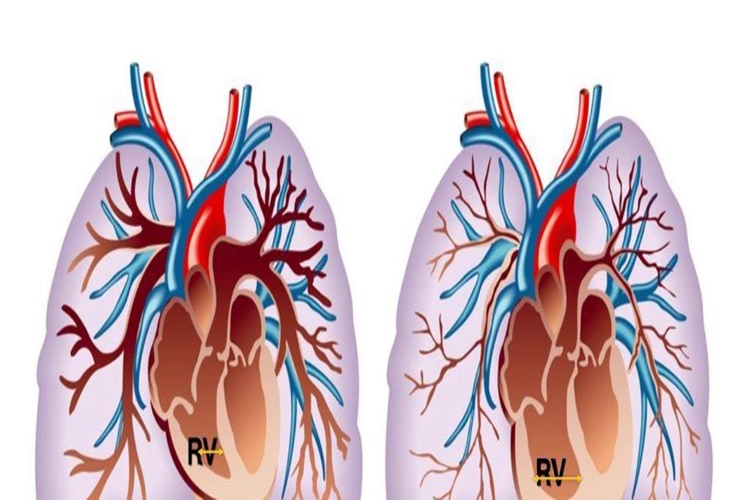

Yüksek Tansiyonun Tedavisi Var Mı?

Evet, yüksek tansiyonun tedavisi mevcuttur. Tıbbi terimle

hipertansiyon olarak adlandırılan yüksek tansiyon, kan damarlarındaki kan basıncının

normalden yüksek olması durumunu ifade eder. Yüksek tansiyon, kalp hastalığı,

inme, böbrek sorunları ve diğer sağlık sorunları riskini artırabilir, bu

nedenle erken teşhis ve tedavi önemlidir.

Yüksek tansiyon tedavisi aşağıdaki yöntemleri içerebilir:

Yaşam Tarzı Değişiklikleri: Yüksek tansiyonun yönetimi ve

kontrolü için yaşam tarzı değişiklikleri önemlidir. Bu değişiklikler şunları

içerebilir:

Sağlıklı bir diyet uygulamak (Düşük tuz, düşük doymuş yağ,

yüksek lifli yiyecekler tercih edilir).

Fiziksel aktiviteyi artırmak (haftada en az 150 dakika orta

yoğunlukta aerobik egzersiz yapmak).

Alkol tüketimini sınırlamak veya bırakmak.

Sigara içmemek.

Stresi yönetmek ve gevşeme tekniklerini uygulamak.

İlaç Tedavisi: Yaşam tarzı değişiklikleri yeterli olmadığında

veya tansiyon çok yüksekse, doktorlar ilaç reçete edebilirler. Yüksek tansiyon

ilaçları, kan basıncını kontrol altına almak için farklı mekanizmalarla

çalışır. İlaç seçimi, hastanın özel durumuna ve sağlık geçmişine bağlı olarak

değişebilir.

Düzenli Takip ve Kontroller: Yüksek tansiyonu olan kişilerin

düzenli olarak doktorlarıyla iletişim halinde olmaları önemlidir. Tansiyon

ölçümleri ve ilaçların etkinliği düzenli olarak kontrol edilmelidir.

Tuz İçeriğinin Azaltılması: Tuz tüketiminin azaltılması,

yüksek tansiyonu olan kişiler için önemlidir. Tuz, kan basıncını artırabilir,

bu nedenle düşük tuzlu diyet uygulanması tavsiye edilir.

Yüksek tansiyonun tedavisi için uygun bir plan, hastanın

tansiyon seviyelerine, yaşına, cinsiyetine ve genel sağlık durumuna bağlı

olarak belirlenir. Tedaviye erken başlamak ve doktor tavsiyelerine uymak,

komplikasyonları önlemek veya riskini azaltmak için çok önemlidir.

Yüksek tansiyonun ciddi sağlık sorunlarına yol açabileceği

göz önüne alındığında, yüksek tansiyon riskiniz varsa veya yüksek tansiyonunuz

olduğunu düşünüyorsanız, bir sağlık profesyoneli ile iletişime geçmelisiniz.

Hastalığınızın derecesine ve tıbbi geçmişinize göre en uygun tedavi planını

belirlemelerine yardımcı olabilirler.